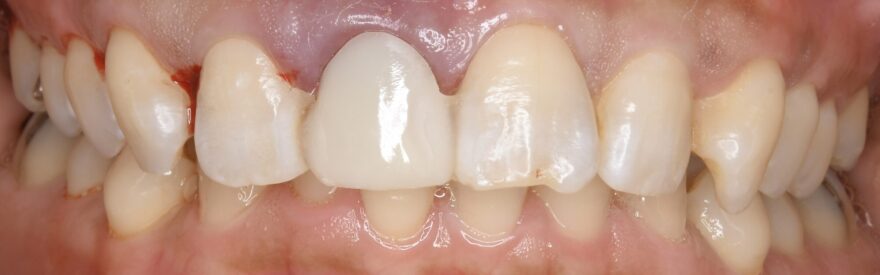

治療後の口腔内写真とレントゲン写真

この症例の治療期間

3ヶ月

この症例の治療費

前歯プレミアムインプラント 495,000円(税込)

この症例のリスク

インプラント治療には「腫れ・痛み・違和感・出血・感染」などのリスクがあります。

また、稀にインプラントと骨が結合しないことがあります。

もし万が一、インプラントと骨が結合しない場合は、すぐに再埋入手術を無料で行わせて頂きます。